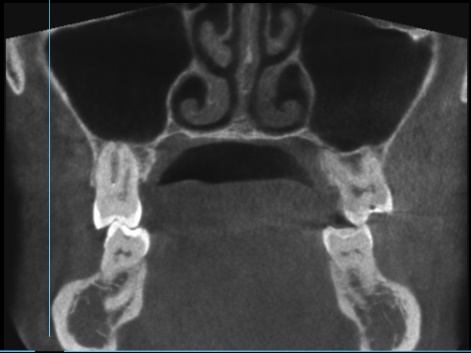

Пропила 2 курса антибиотиков. Хирург сказал, что все зубы в порядке, и отправил домой нервы лечить. Рентгенолог увидела повреждения и сказала не есть больной стороной и вообще не жевать. Это избавило меня от постоянной боли. Но стоит только дотронуться до семёрки, появляется неприятное очущение, как будто он висит на волоске. И в месте удалённой 5 зуд. Как будто кость сломана. Фото с 3д рентгена во время курса антибиотиков.

По этому снимку можно сказать, что немного повреждена передняя стенка, но это не является проблемой. К хирургу обратиться стоит, для того чтобы оценить процесс заживления.